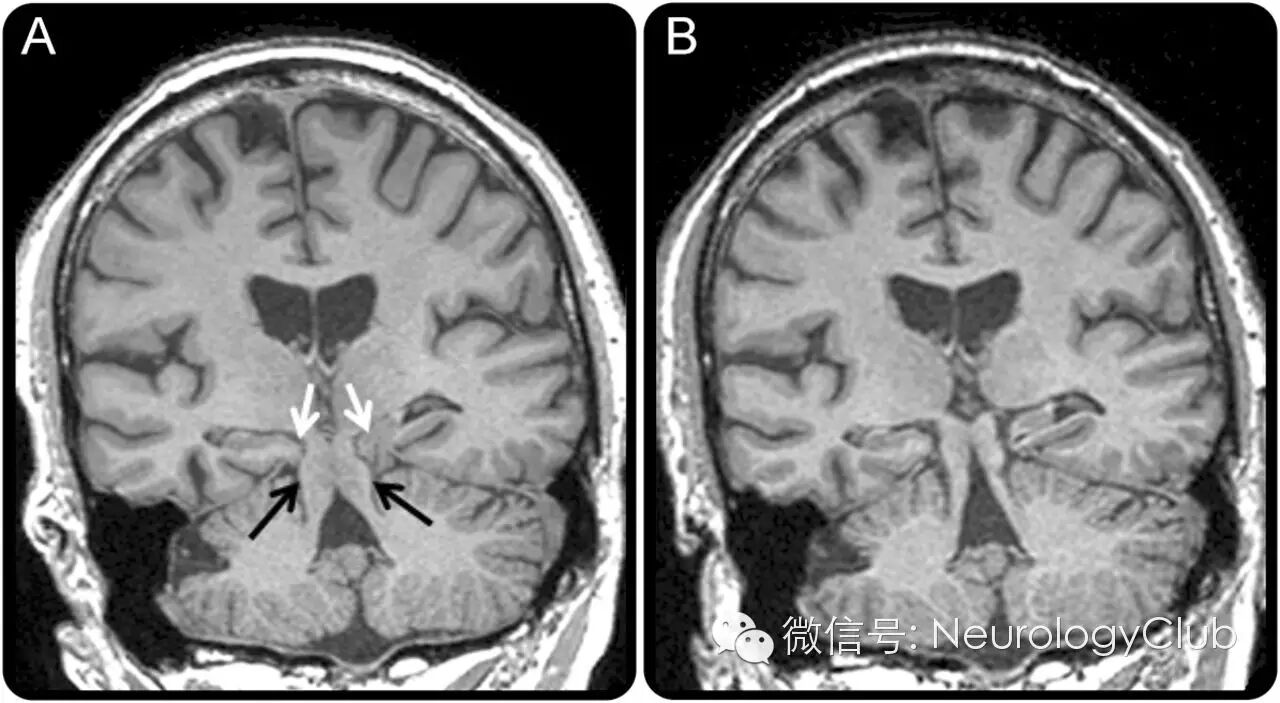

71岁男性,健忘,行为改变,咆哮震撼发声,直立性头痛和咳嗽6年。头颅MRI符合额颞叶脑下垂综合征(frontotemporal brain sagging syndrome)(图A)。随后他不小心摔倒,胸部撞到了椅子上,神奇的是,咳嗽立即缓解,认知功能改善,影像学上见下垂脑组织复位(图B,视频如下)。

(A:黑箭头示中脑下移低于小脑幕;白箭头示后海马旁回和舌回疝出;B:复查提示脑干及颞叶内侧结构复位)